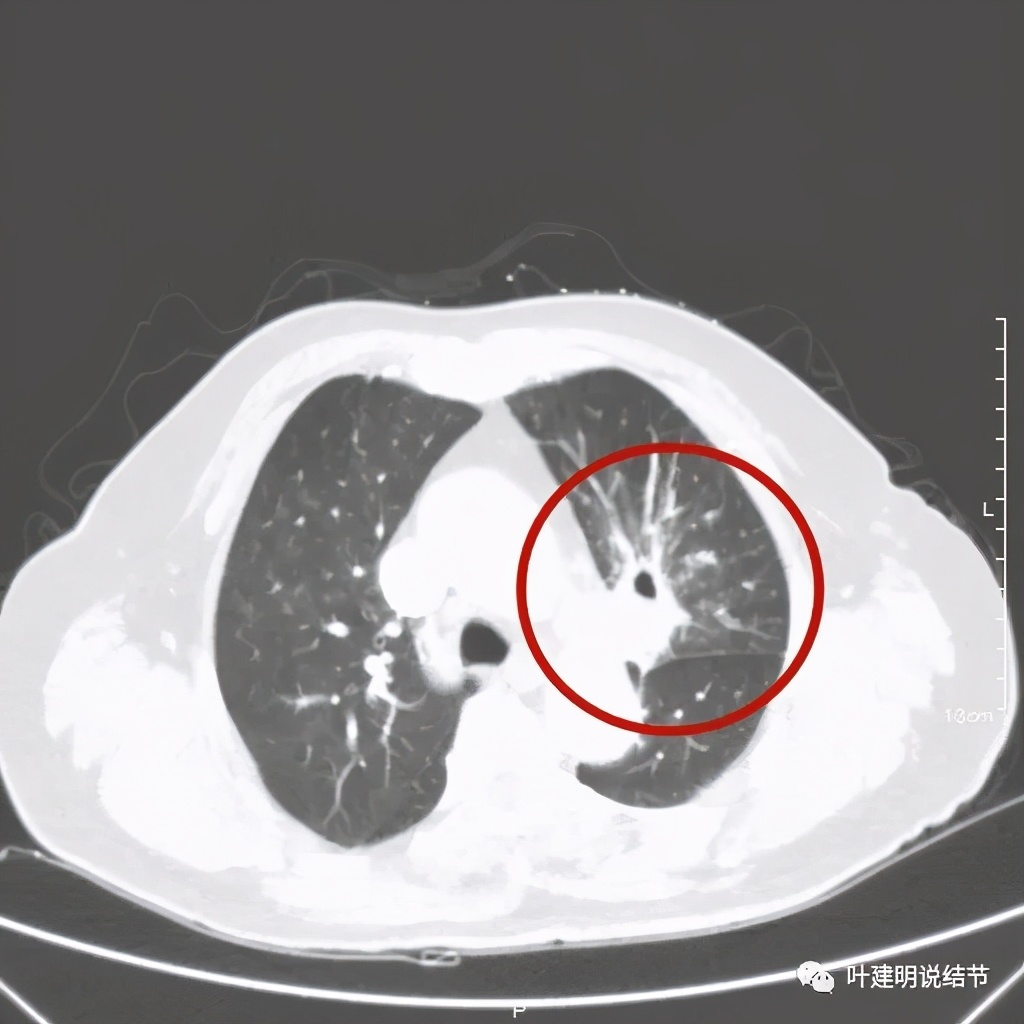

肺窗见原左上叶巨大占位已经明显缩小,甚至几乎不见了!而且上图示左上叶支气管清晰可见,内壁变光滑。纵隔窗增强又是如何的呢?

我样的治疗效果,显然超出了我们之前的预期,那么接下来拟选择行手术治疗,初定左上叶袖式肺叶切除加淋巴结清扫,但因为肺门区仍有软组织影,与肺动脉的关系仍密切,肿瘤与肺动脉间能否游离开来还是未知数,但至少得努力争取,鉴于患者年纪虽大,肺功能指标尚可,血气分析也基本正常,所以与患方沟通后确定行手术探查,但也也说明有万一全肺切除的可能(虽然这种可能性较小)。